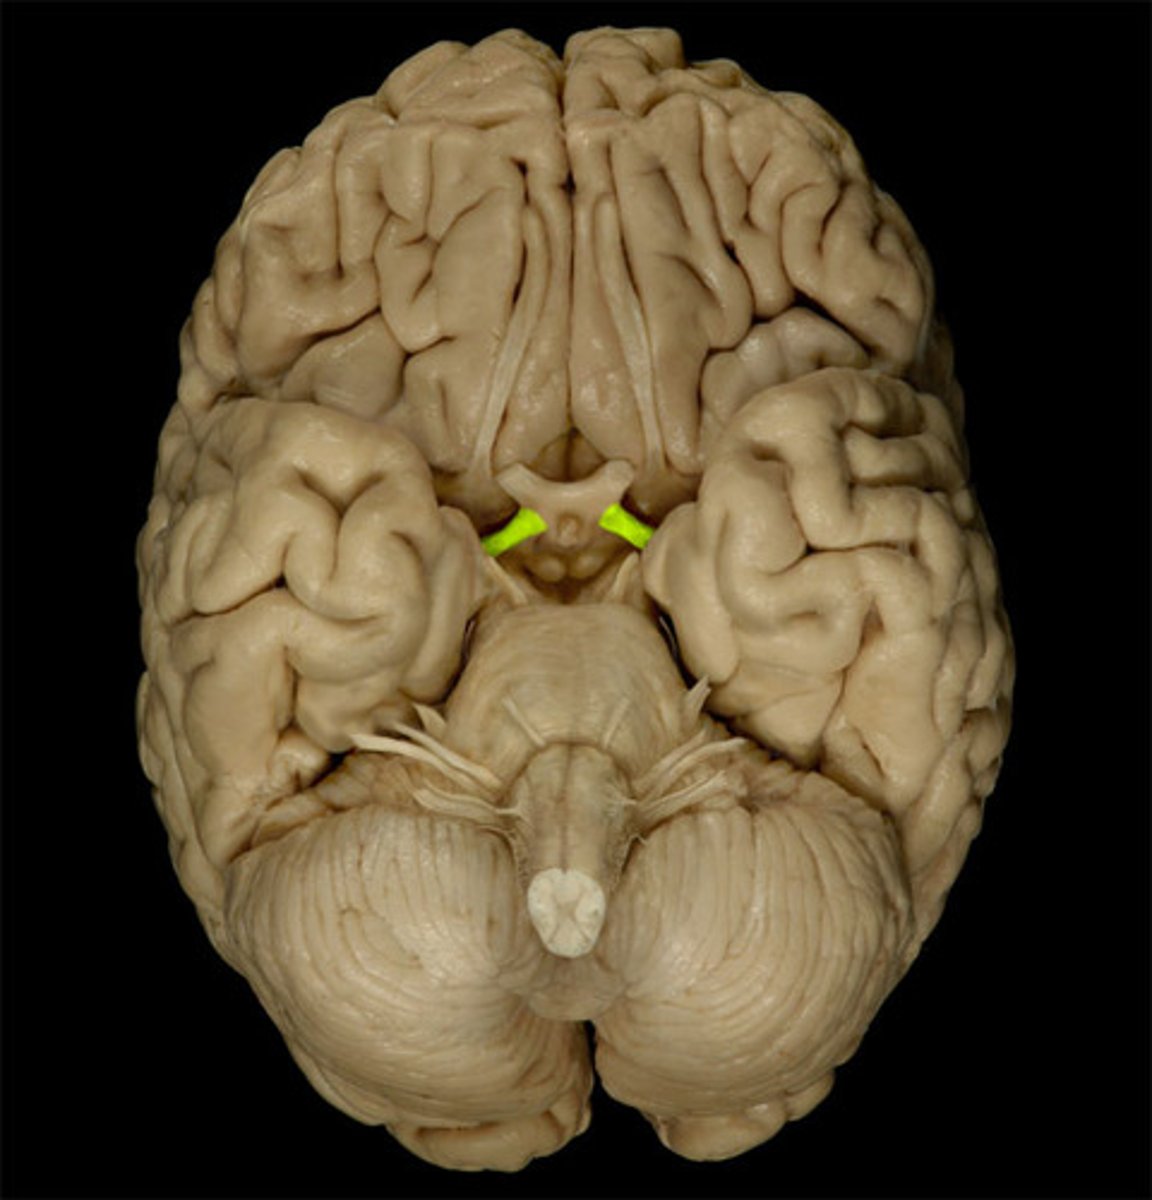

trochlear nerve (CN IV)

Motor cranial nerve that controls movement of the eye inferiorly and laterally; innervates superior oblique muscle

midbrain (mesencephalon)

a small part of the brainstem above the pons that integrates sensory information and relays it upward

cerebellum

the "little brain" at the rear of the brain; functions include processing sensory input and coordinating movement output and balance